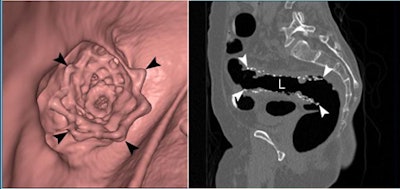

![]() |

| CTC was successful in a 58-year-old woman with a flexible metal stent in the rectosigmoid junction. All images courtesy of Dr. Seong Ho Park. |